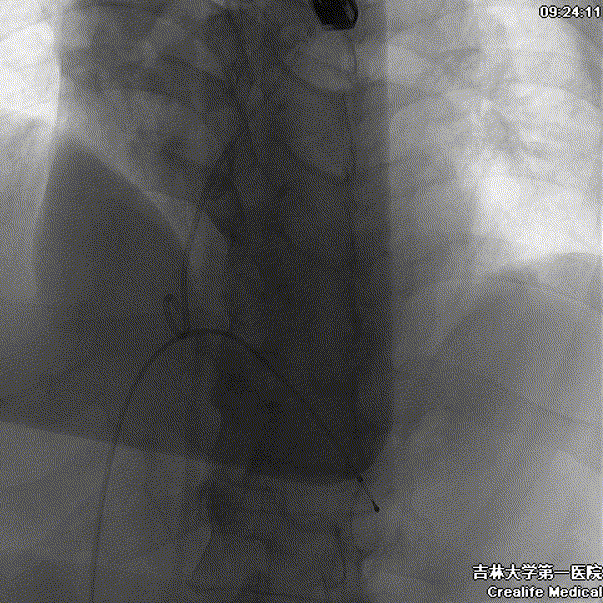

术中影像

主动脉根部造影

瓣膜工作位造影

瓣膜形态良好 位置理想

少量瓣周漏 平均跨瓣压差7mmHg